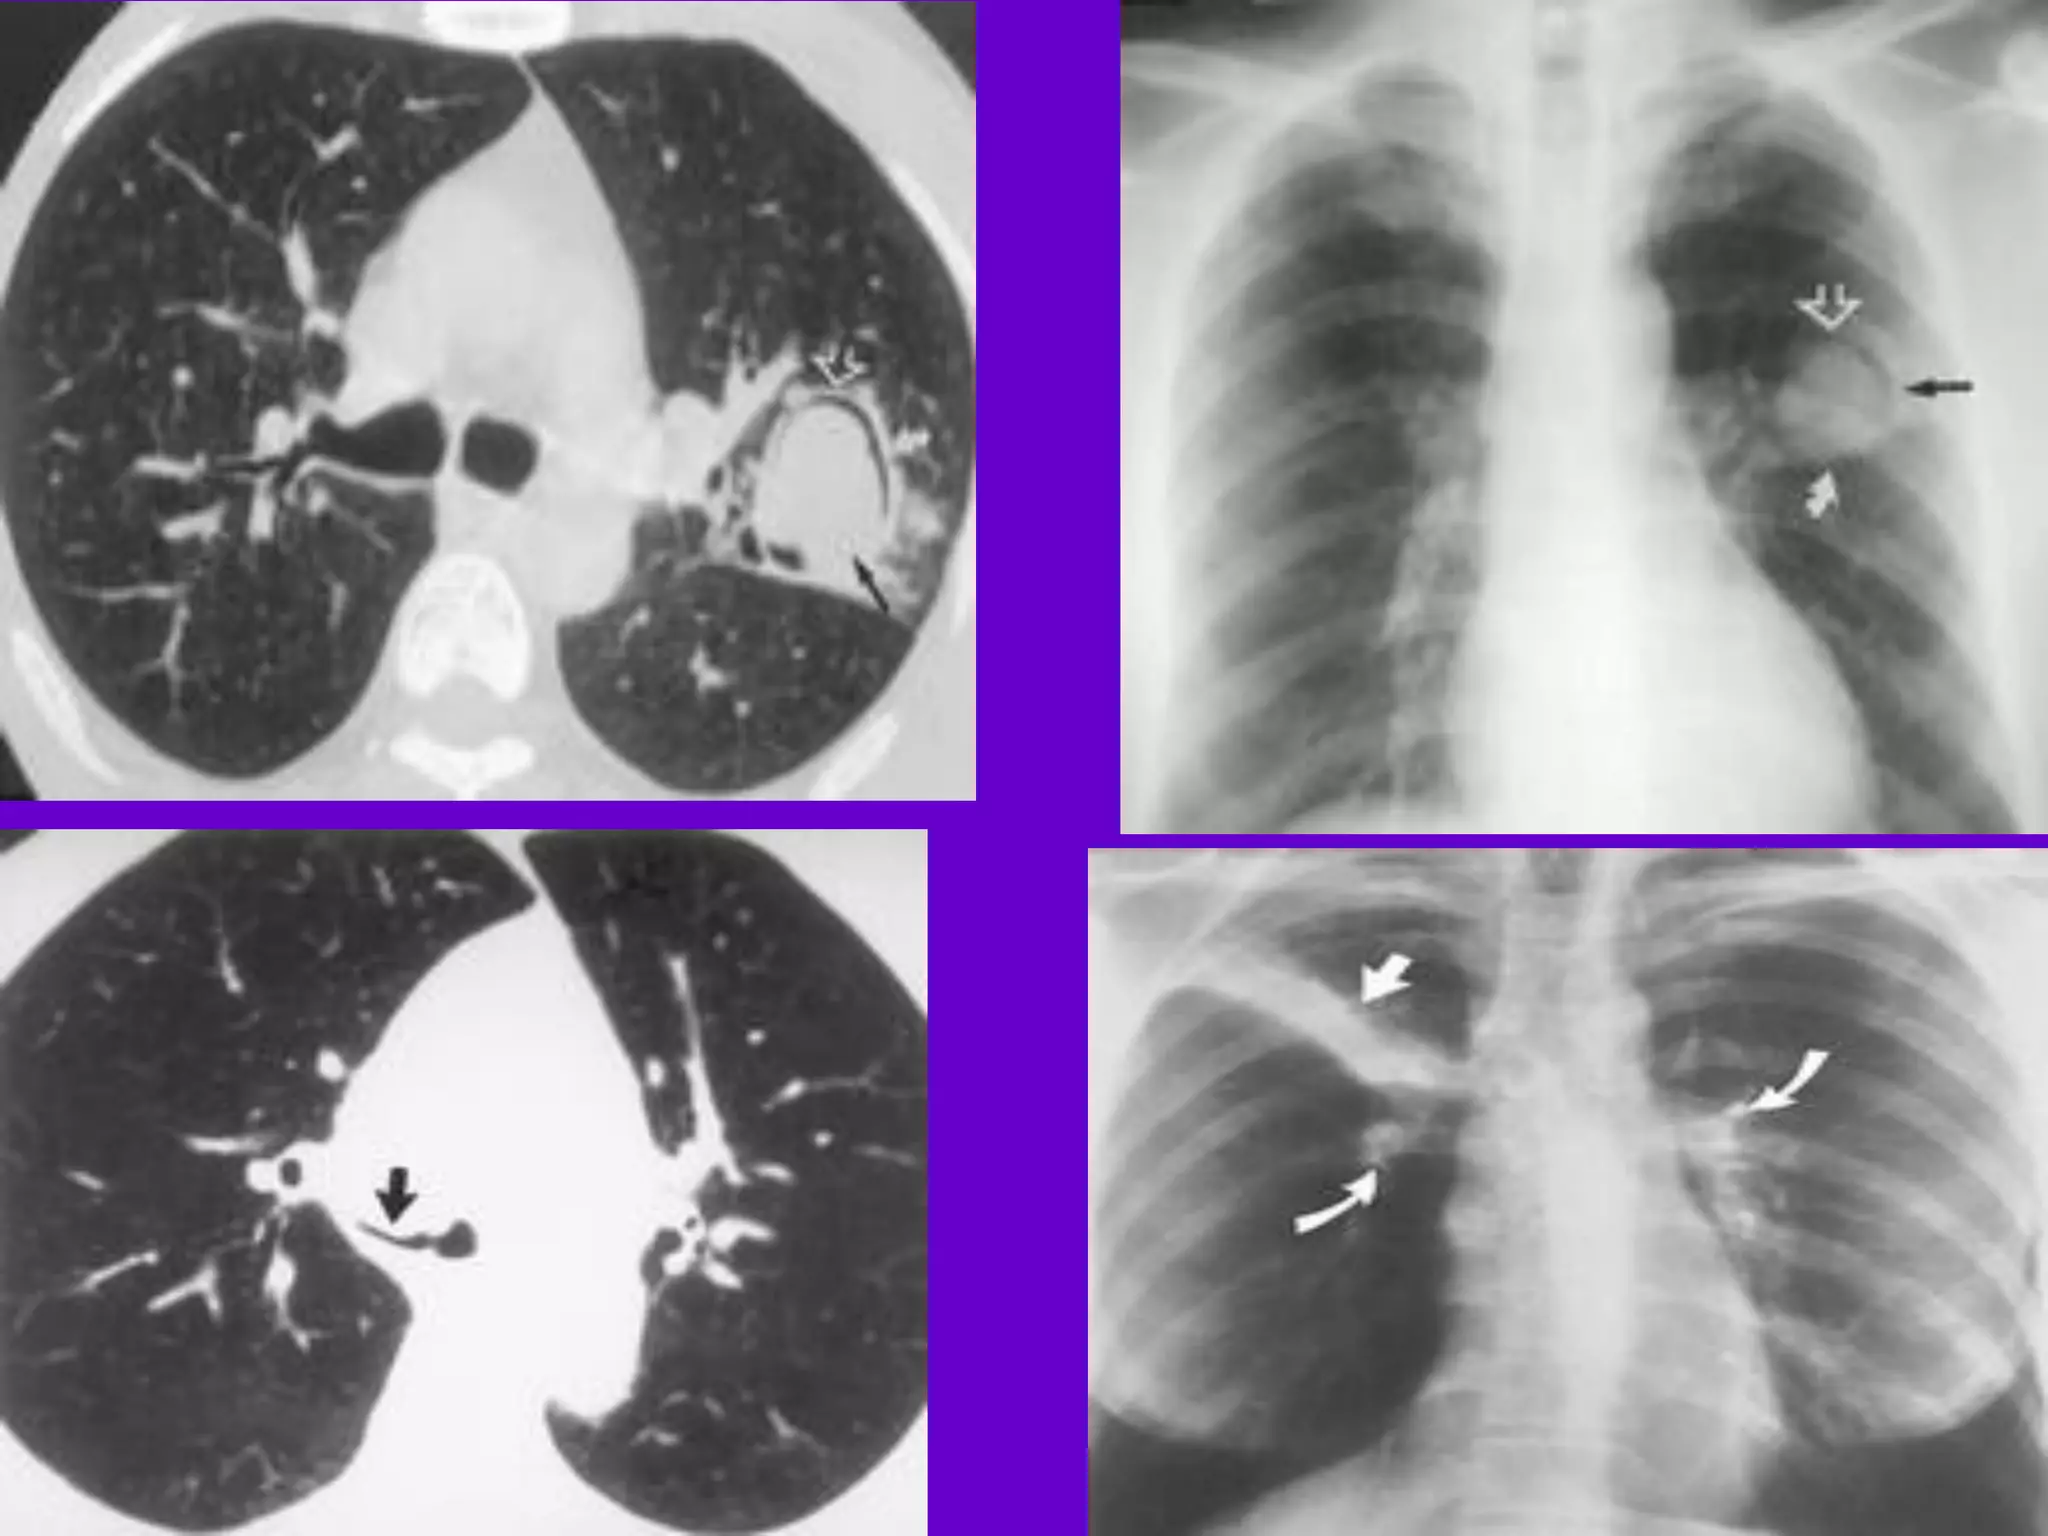

Pulmonary TB :

Lobar Pneumonia

􀂄

CT is superior than plain CXR in picking

up the

consolidation, atelectasis and the hilar LN

thereby

making the diagnosis easy.

􀂄 MRI reveals some of these changes,

however, CT is

the diagnostic modality of choice in such

cases.

Bronchopneumonia

On CT it is usually B/L and widespread,

not always

symmetrical involvement of lungs.

Hilar and Mediastinal

Lymphadenopathy

CT and MRI depict the hilar and

mediastinal LN

equally well.

􀂄 Calcification in the nodes is however

better seen on

CT.

􀂄 Necrosis is seen as focal areas of low

attenuation on

a CECT.

􀂄 On MRI focal necrosis is seen as areas

of increased

signal intensity on T2W images.

EBTB

HRCT is sensitive in the detection of

early

endobronchial spread of disease.

Miliary TB

􀂄 Earliest form of miliary TB is detectable

on HRCT.

􀂄 Coalescing nodules result into patchy

irregular

opacities and HRCT shows this variation

effectively

and has been described as “snowstorm

appearance”.

􀂄 HRCT shows cavitation, which is not

evident on plain

CXR.